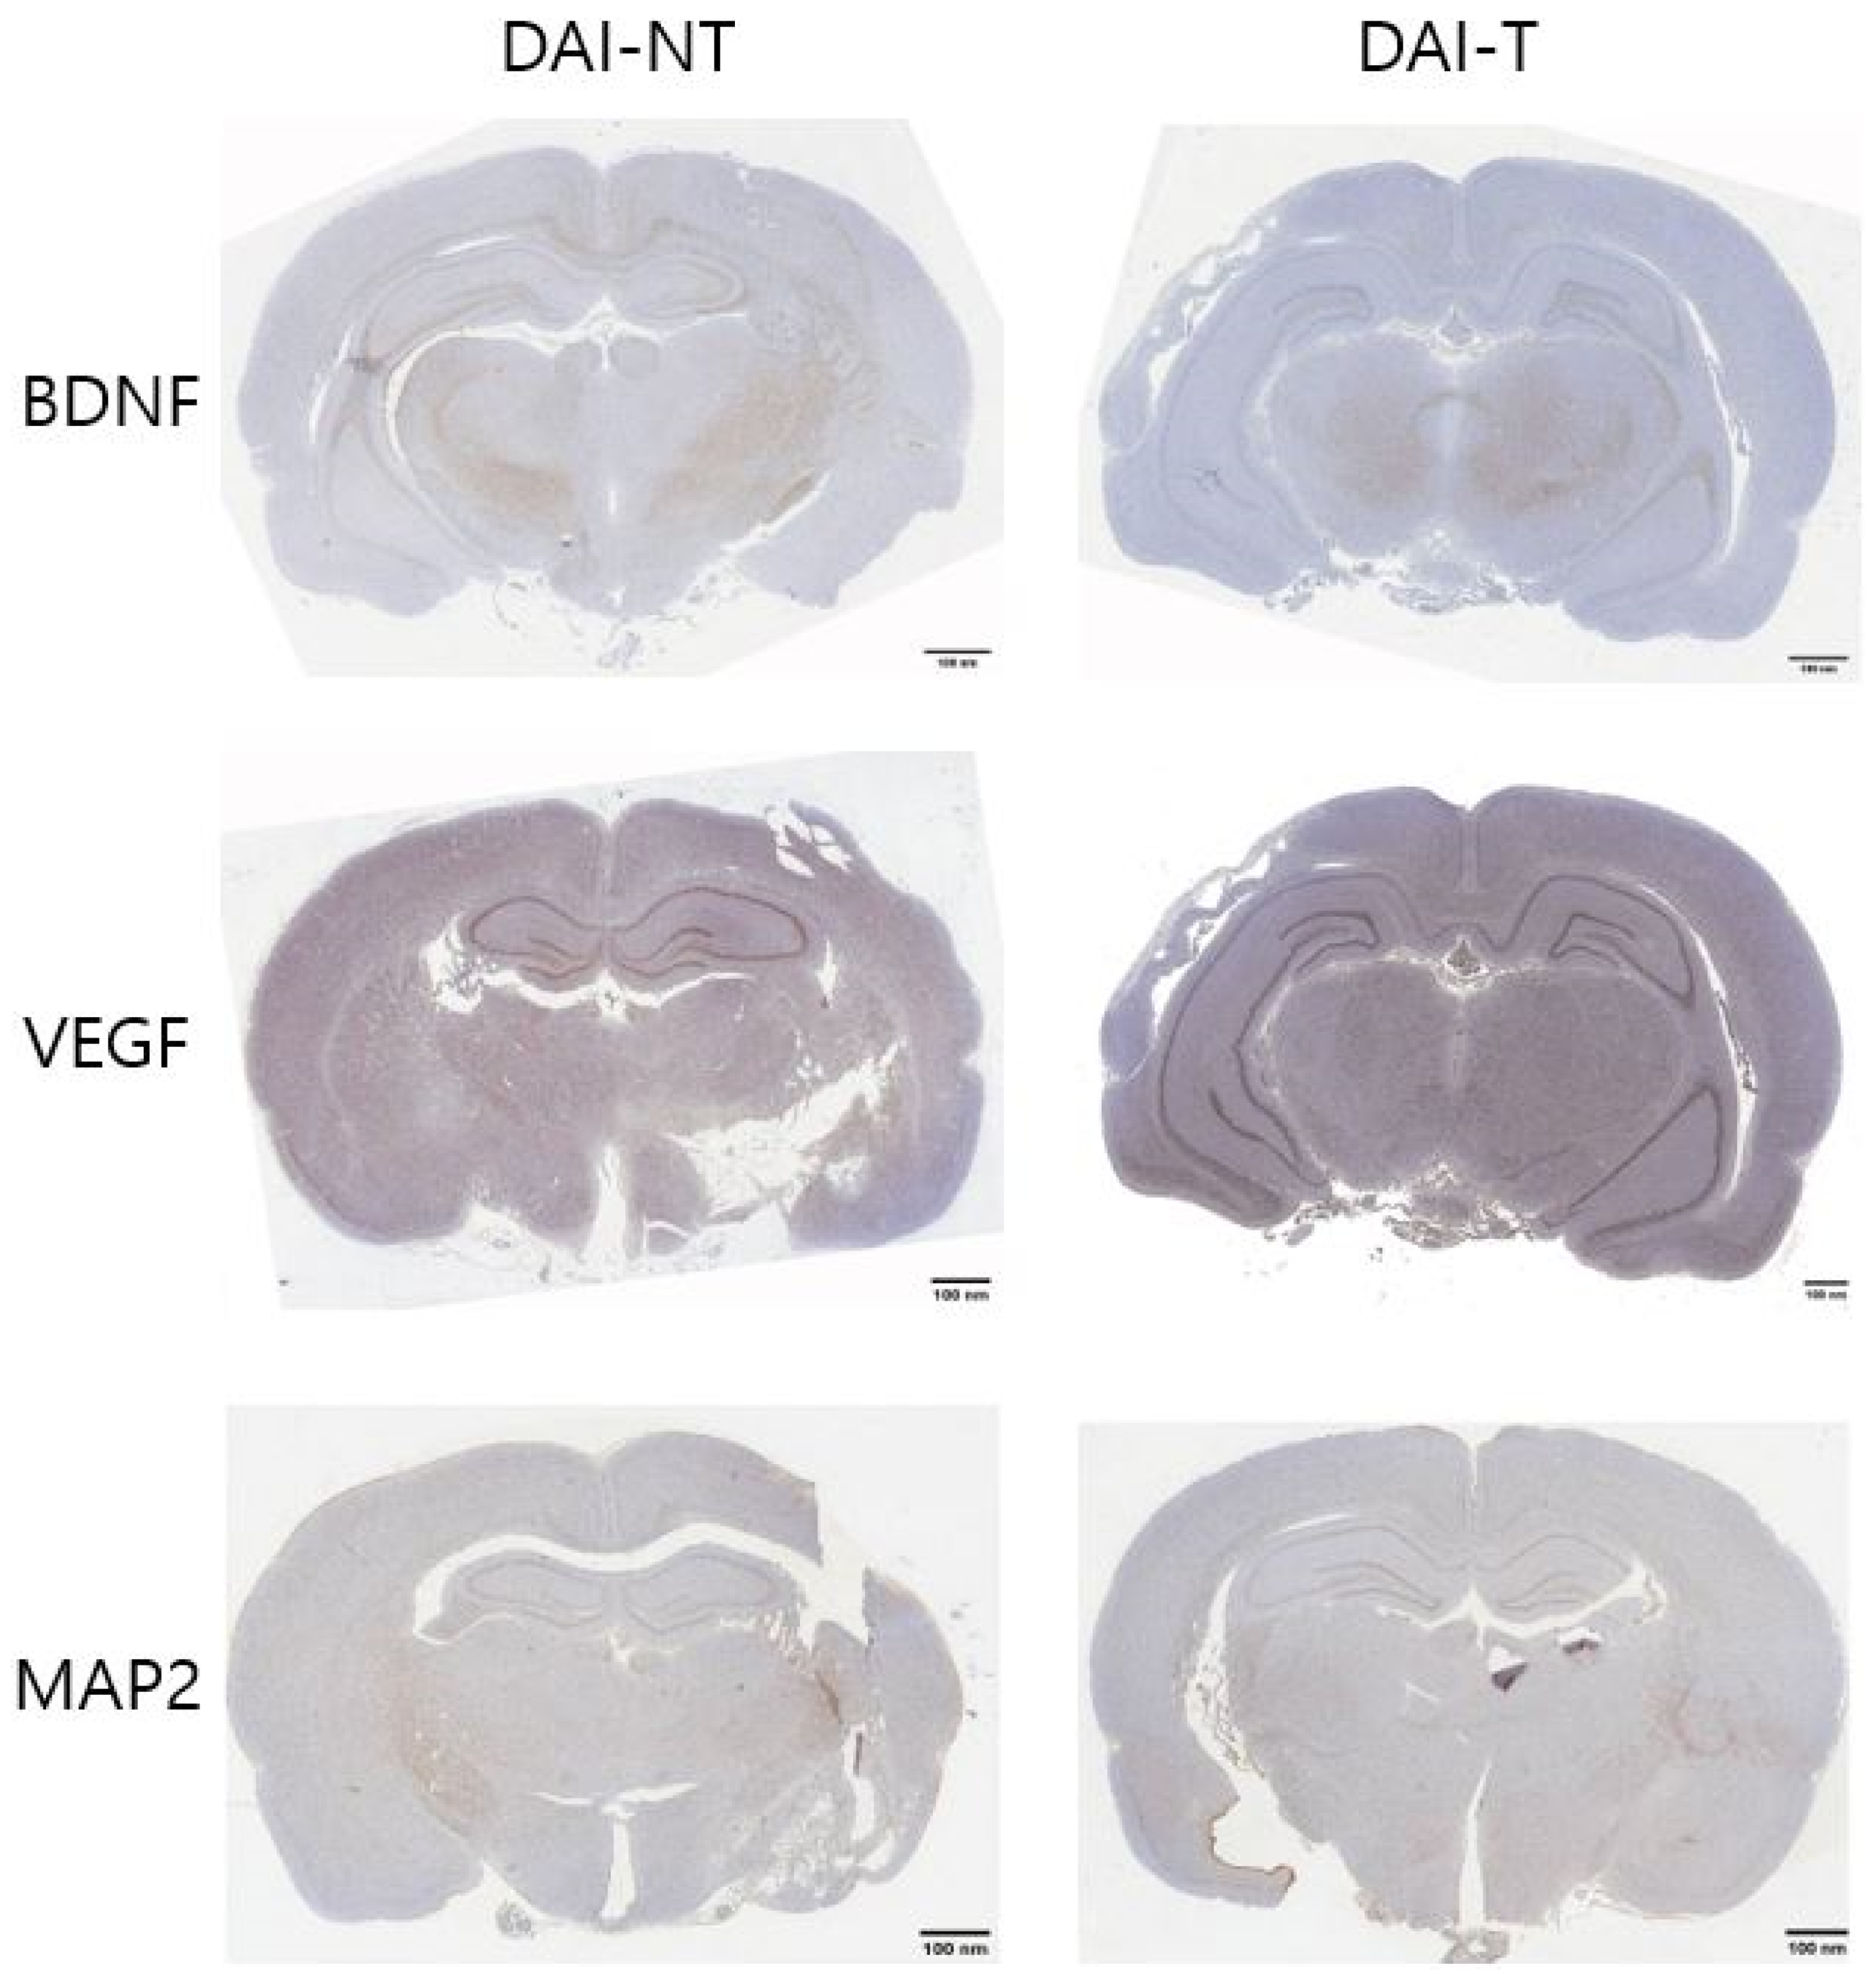

4.3. Immunohistochemistry

Figure 2 and Figure 5 show the immunohistochemistry analysis. The ratio of BDNF immunoreactivity in the hippocampal area compared to the total area was 5.008% in the DAI-NT group and 8.778% in the DAI-T group. The ratio of VEGF immunoreactivity in the hippocampal area compared to the total area was 8.711% in the DAI-NT group and 12.105% in the DAI-T group. The ratio of MAP2 immunoreactivity in the hippocampal area compared to the total area was 10.475% in the DAI-NT group and 12.814% in the DAI-T group (Table 1).

Immunohistochemical studies showed that BDNF, VEGF, and MAP2 were more expressed in the hippocampal region adjacent to the injury in the DAI-T group than in the DAI-NT group.

Figure 2.

Immunohistochemical detection of the brain-derived neurotrophic factor (BDNF), vascular endothelial growth factor (VEGF), and microtubule-associated protein 2 (MAP2) expression in the hippocampus after rTMS in a DAI rat. In the immunohistochemistry for BDNF, VEGF, and BAP2 for the hippocampal area, the DAI-T group displayed the most significant immunoreactivity for BDNF, VEGF, and MAP2 compared to the DAI-NT group (×100).